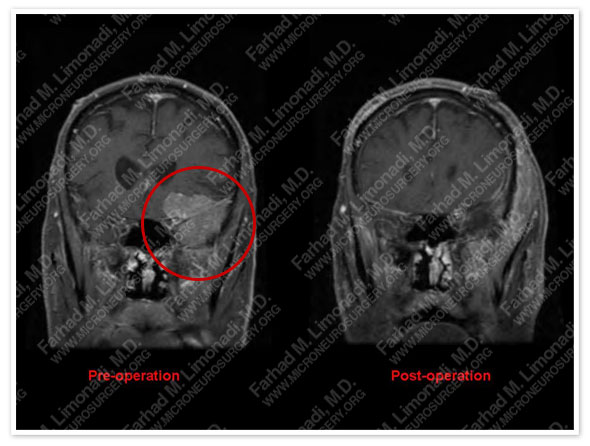

MRI scan of the patient's brain showed a large intrinsic brain tumor in left (dominant) hemisphere pressing on speech area (Broca’s region).

Post-op Course

- Patient was immediately able to speak and communicate again after the operation and was discharged from the hospital in good health and with no postoperative complications.